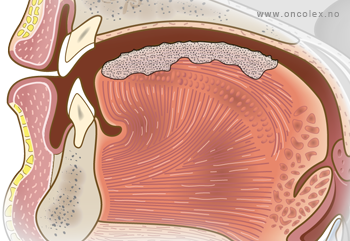

T3: Svulster på 4-6 cm i største diameter.

- T3 – svulster på 4-6 cm